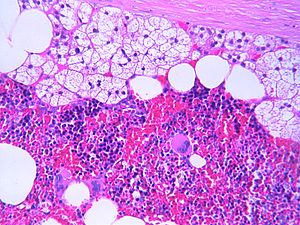

Myelolipoma. H&E stain. | |

| LM | adipose tissue, hematopoietic elements from all three lineages (erythroid, myeloid, megakaryocytic), +/-calcification |

Features:[2]

- Adipose tissue.

- Hematopoietic elements from all three lineages:

- Erythroid.

- Myeloid.

- Megakaryocytic.

- +/-Calcification.[1]

The sections shows a lesion with bland adipocytes and hematopoietic elements (erythroid, myeloid, megakaryocytic) that is surrounded by a thin rim of adrenal cortex and a partial fibrous pseudocapsule. Significant cellular atypia is absent. The lesion appears to be clear of the inked margin.